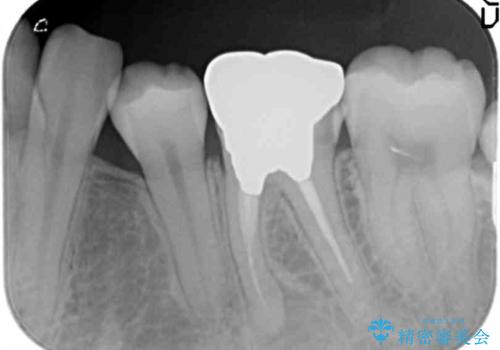

- 左下の銀歯の状態が悪く抜歯してブリッジにした患者様です。

途中全体矯正をはさみ、根の向きが並行になった状態でブリッジを入れることができました。